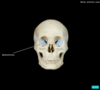

Cranium Flashcards

(33 cards)